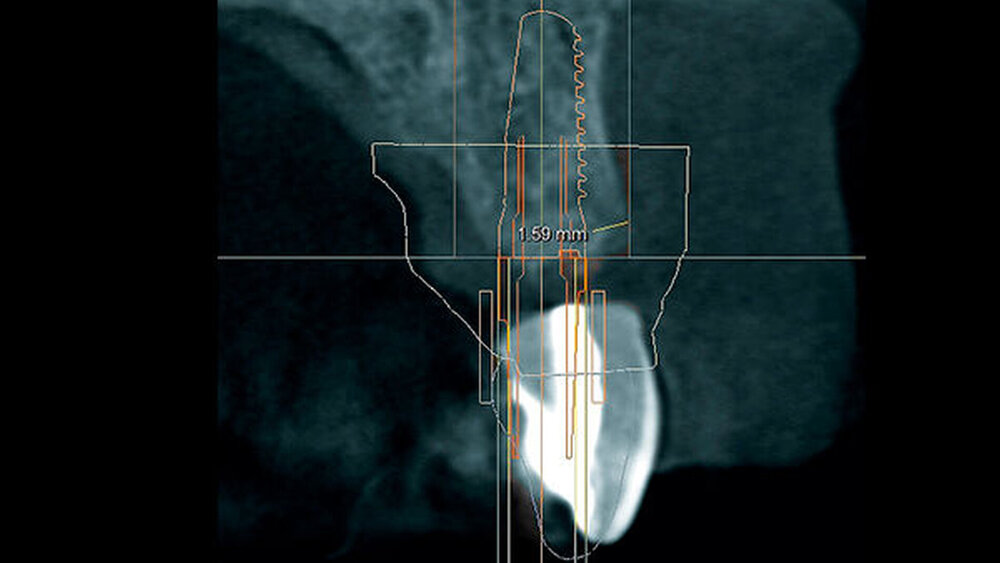

In welchen klinischen Anwendungen bietet das Implantat Vorteile?Hermann:Das neue CAMLOG PROGRESSIVE-LINE Implantat besticht durch sein innovatives parallel-konisches Makrodesign mit einem speziellen Gewinde, bei gleichzeitig bewährter Prothetikschnittstelle der Camlog-Linie. Dies bedeutet, dass in der chirurgischen Phase mit diesem Implantat eine zuverlässige Primärstabilität erzielt werden kann, speziell bei schwierigen anatomischen Voraussetzungen, wie z. B. bei der Sofortimplantation, bei reduzierter Kieferkammbreite oder konkav verlaufenden Alveoloarkämmen sowie bei weichem Knochen im Oberkiefer. Aufgrund des krestalen Verankerungsgewindes sehen wir zudem einen Vorteil bei der Platzierung des Implantats im Zusammenhang mit einer simultanen, offenen Sinusbodenelevation bei stark reduzierter Restknochenhöhe (2–3 mm). Auch einzeitige Verfahren lassen sich einfacher durchführen. Denn auch im kompromittierten Knochen erreicht das Implantat eine hohe vorhersagbare Primärstabilität.

Sind dann auch eher Sofortversorgungsprotkolle umzusetzen?Hermann:Die erzielte Primärstabilität ist in den meisten Fällen so hoch, dass eine sofortige provisorische Versorgung/Belastung möglich ist. Somit können wir unseren Patienten effiziente Behandlungsabläufe anbieten. Die Effizienz zeigt sich beispielsweise auch bei der Reduktion der Bohrschritte durch ein flexibles Bohrprotokoll. Gerade im weichen Knochen benötigen wir meist nur drei Bohrschritte bis zur Insertion des Implantats und erzielten eine exzellente Primärstabilität durch eine geringere Aufbereitung des Implantatbetts. Auf den zusätzlichen Einsatz nicht-ablativer Techniken (Osteotome) kann häufig verzichtet werden. Ein Teil der 80 von uns gesetzten PROGRES ‧ SIVE- ‧ LINE Implantate befindet sich bereits in der prothetischen Nachkontrolle. Das klinische und prothetische Outcome ist hervorragend. Es gibt weder chirurgische Komplikationen noch Probleme bei der Einheilung, und die prothetische Versorgung funktioniert perfekt.